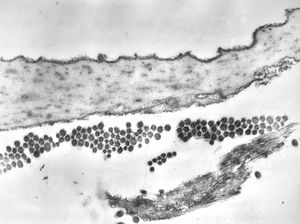

M,7m. | Birbeck granules (Langerhans granules, X-granules) - skin, histiocytosis X

M,7m. | Birbeck granules (Langerhans granules, X-granules) - skin, histiocytosis X